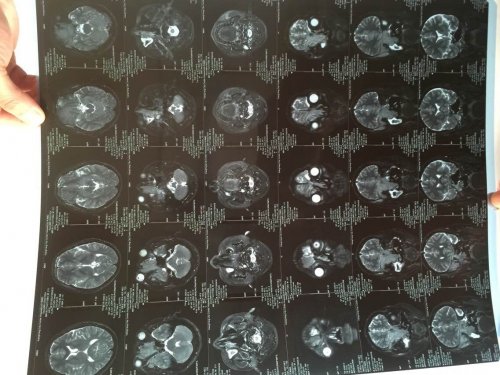

04—15 影像图

04—15 影像图